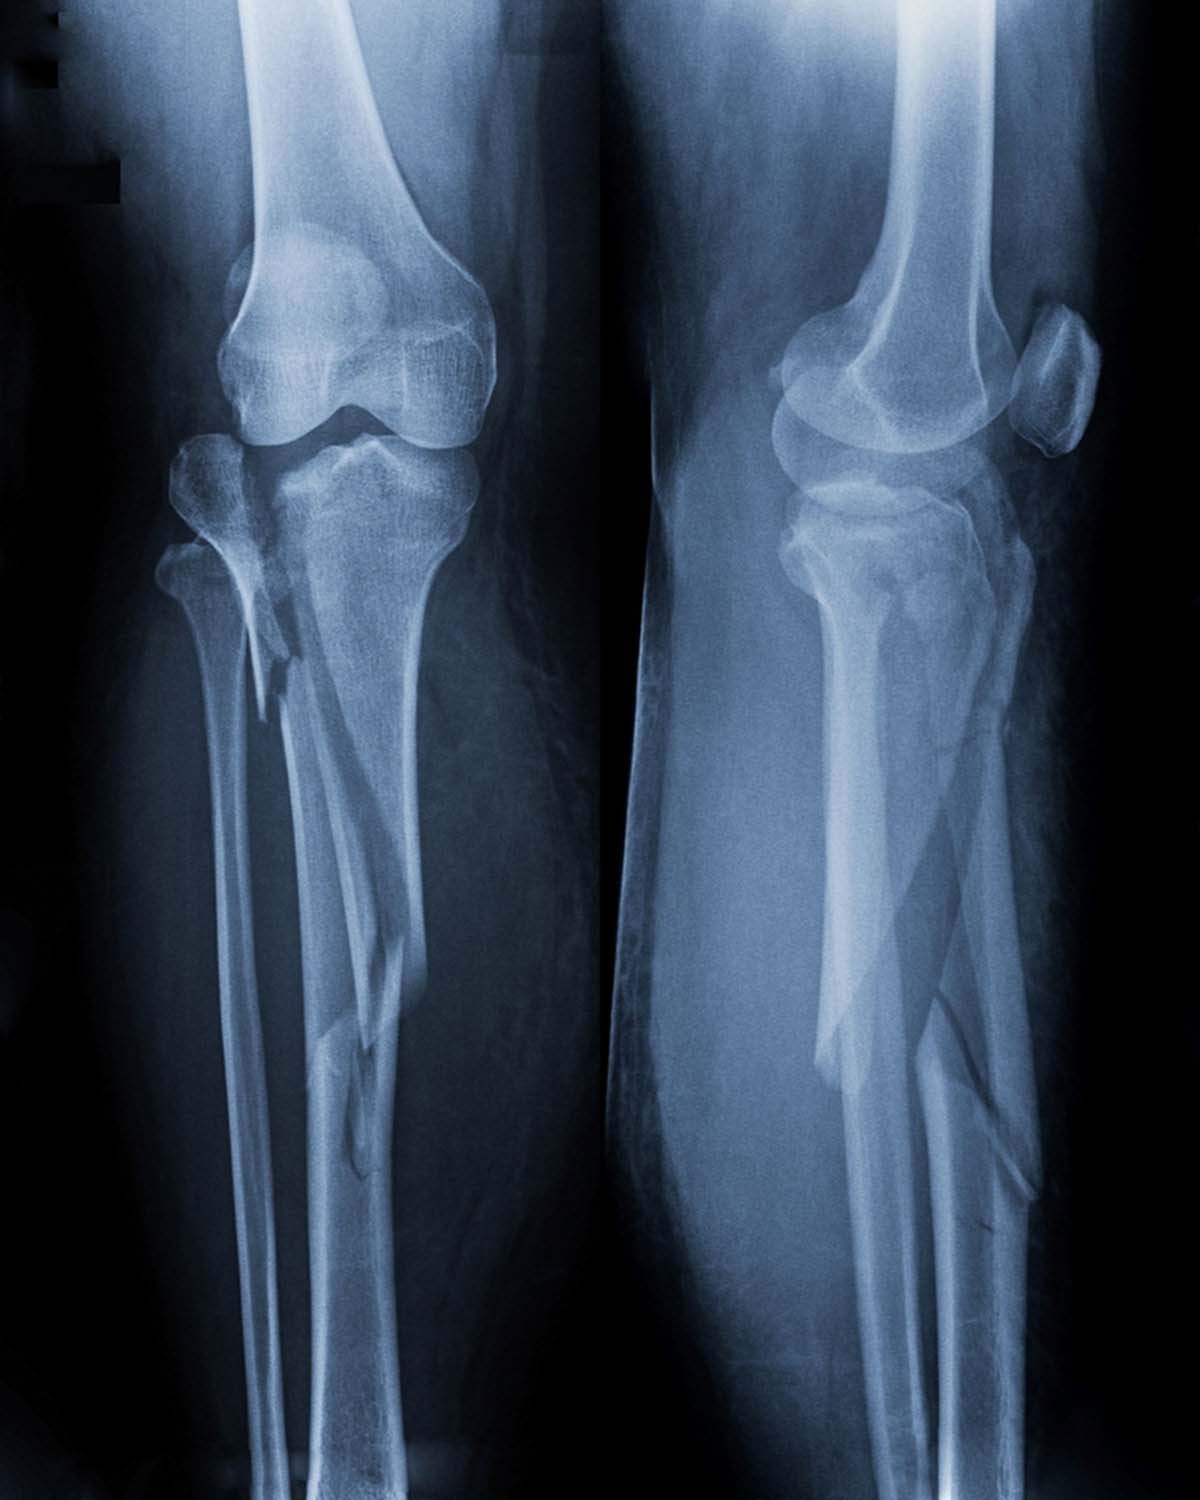

Knee Fracture

What is Knee Fracture Surgery?

Fractures of the lower end of thigh bone (distal femur), upper end of

tibia (proximal tibia) or the knee cap (patella) constitute knee fractures.